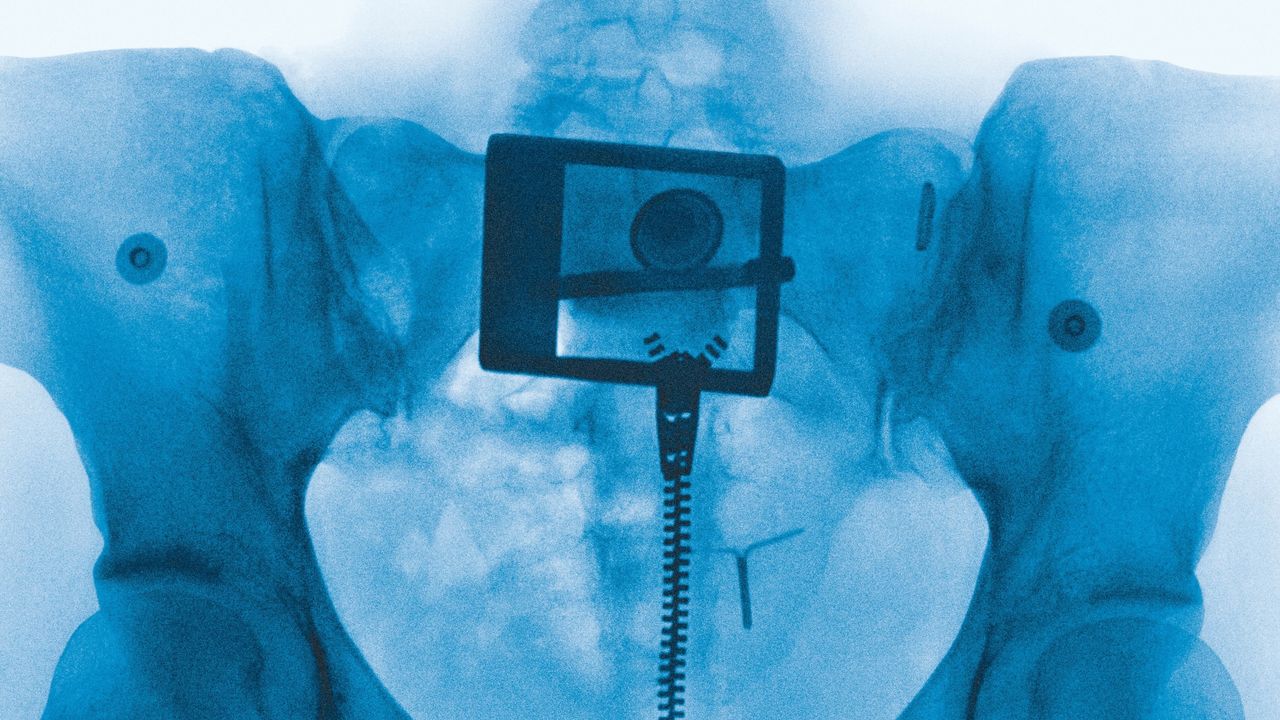

That last vignette comes from “Clearblue,” a spare swirl of vocoder melody à la Imogen Heap. It’s all Lorde’s voice, words running across her tongue like ribbons curling against a blade as she recounts a pregnancy scare that blurred the boundaries between intimacy and independence. The incident passes, becoming a precious reminder of her own vitality; the test a relic, lost to the trash. But the topic of motherhood remains potent. The presence of Lorde’s mom, the poet Sonja Yelich, is felt across the album—particularly on “Favourite Daughter,” a bubbly number where Lorde imagines her own career as the fulfillment of her mother’s ambitions. Lorde’s choice of album cover, too, is meaningful: Heji Shin, the photographer who X-rayed her pelvis, is perhaps best known for her raw images of crowning newborns. Documents of the grotesque and generative potential of the human body, they can also be read as metaphors for the bloody labor of creativity.